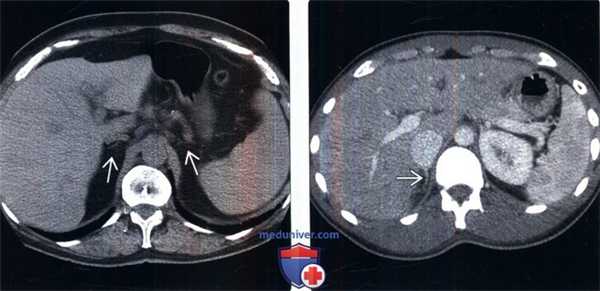

(Слева) У женщины 71 года с аутоиммунным полиэндокринным синдромом (недостаточность надпочечников, гипотиреоз) на бесконтрастной КТ выявлено уменьшение надпочечников Интересно, что данная пациентка также имела в анамнезе длительное течение саркоидоза, что служит дополнительной причиной первичной и вторичной (гипофизарной, гипоталамической) надпочечниковой недостаточности.

(Справа) Молодой мужчина с острой надпочечниковой недостаточностью, контрастная КТ: едва заметный правый надпочечник. После стимуляции козинтропином сывороточный кортизол не обнаружен.